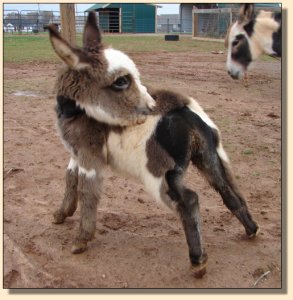

Update

9/25/07 @ 10pm - Bow and Pony-Tailed Lass are at UT Vet Hospital in Knoxville. The prognosis

is good. Her anus is going to be able to be repaired with an operation but they hear a slight

heart murmur. Her heart will be evaluated further tomorrow to see if she is strong enough

for the operation on Thursday. Stay tuned for updates and keep those prayers coming!

Update - 9/28/07: Bow and Lass are home. They will be returning in three weeks for

the surgery. The vets wanted her newborn skin to be more mature before they operate. You

can see them on our live streaming barn

cam now!